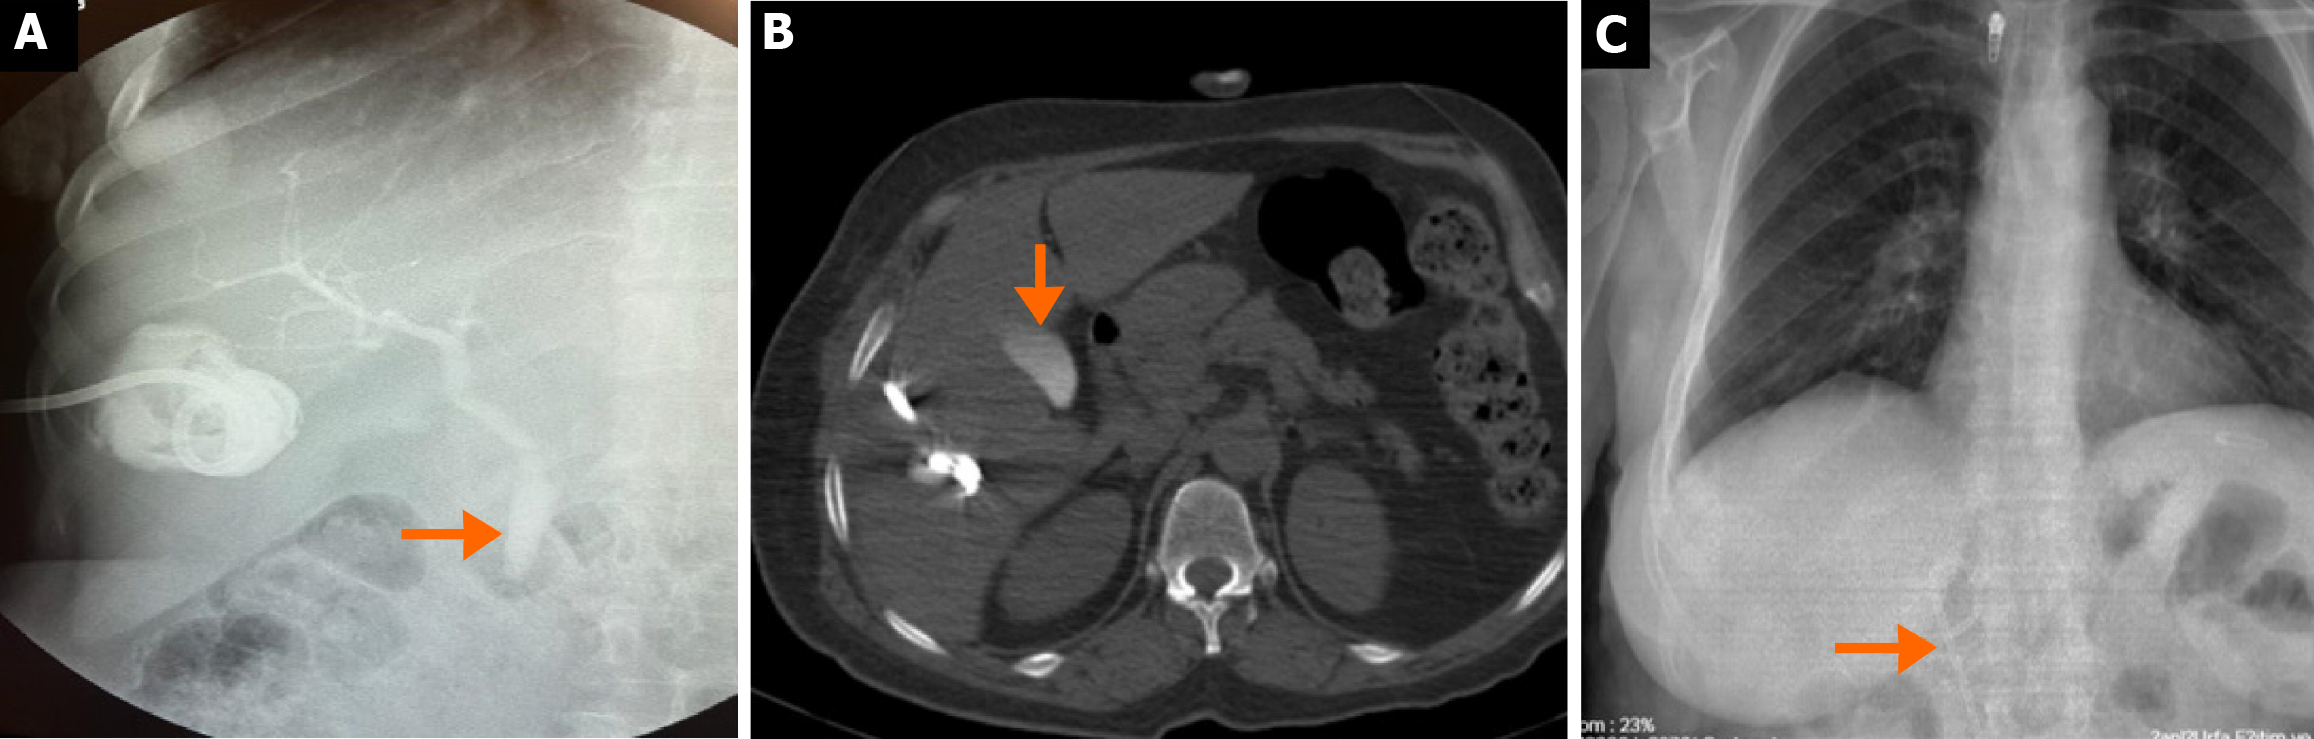

CBFs developed in 15.4% (n = 113/734) of surgically treated patients and 16.8% (n = 43/255) of percutaneously treated patients, with no statistically significant difference (P = 0.651) (Table 3 and Figure 3). Intraoperative bile leakage was identified in 83.2% (n = 94) of surgical patients, with primary suture or clipping performed. Such interventions were not applicable in the percutaneous group (Figure 4). Post-procedural bile drainage via drains or catheters occurred more frequently in the percutaneous group (100% vs 56.6%; P < 0.001). The rate of spontaneous closure of the fistula without intervention was similar in both groups (76.7% vs 73.4%; P = 0.825). The mean time to spontaneous closure was also comparable between the surgical and percutaneous groups (14.2 ± 7.3 days vs 11.7 ± 9.4 days, respectively; P = 0.110). The need for postoperative ERCP due to persistent fistula was significantly higher in the percutaneous group (21.8% vs 8.8%; P = 0.033) (Figure 5). There was no significant difference between the groups in terms of secondary surgical intervention (6.2% vs 4.6%, respectively; P = 1.000). In the surgical group, secondary surgery was required in 7 patients (6.2%) due to persistent fistulas. In the percutaneous group, two patients underwent secondary surgery by personal preference: One underwent left lobectomy and the other partial cystectomy.